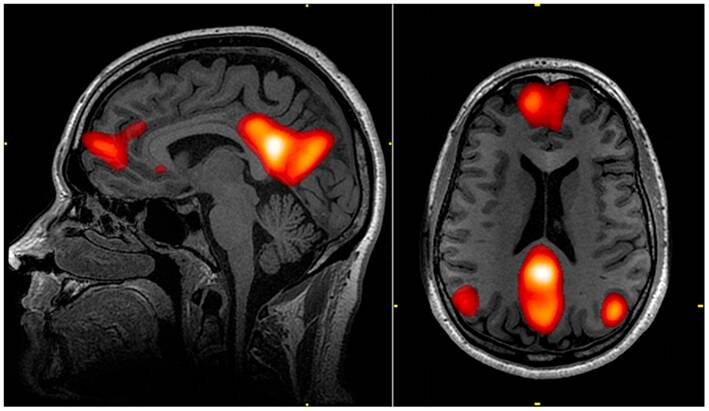

Exploring the Brain’s Default Mode Network

The brain’s Default Mode Network (DMN) is a fascinating area that becomes more active during sensory deprivation. The DMN is associated with self-referential thinking and daydreaming. When external stimuli are removed, the brain tends to focus inward, activating the DMN.

This inward focus is associated with self-referential thinking, mind-wandering, and introspection, which may support creative thinking. Understanding the DMN’s role in sensory deprivation helps us see why these experiences can be so creatively enriching for many individuals.